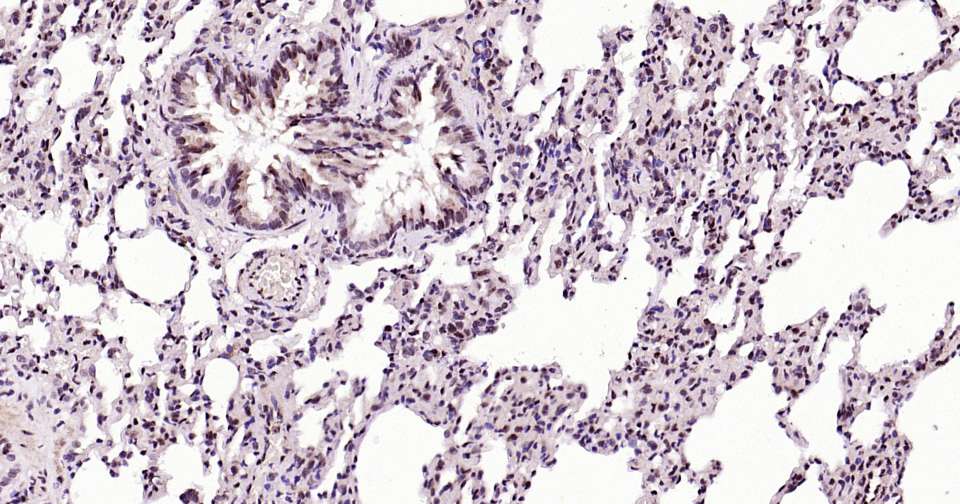

Immunohistochemical analysis of paraffin embedded mouse lung tissue slide using IHC0387 (phospho-STAT3 (Ser727) Kit).